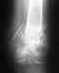

Здравствуйте! У моей мамы больше одного месяца назад был перелом руки в районе плеча со смещением - прошу прощения за неточность формулировки, к сожалению нет под рукой более точной информации. Она лежала один месяц на вытяжке, после чего ей наложили лангет. Гипс ей должны снять девятого июня, и, хотя раньше (основываясь на снимке, сделанном после вытяжки) врач говорил, что вероятность операции крайне мала, сейчас врач (другой, предыдущий ушел в отпуск) говорит что операция возможно будет необходима, возможно ее придется делать в ноябре-декабре (когда образуется "мозоль"). В случае необходимости операции, мы хотим делать ее в вашей организации. Вопрос у меня такой. Основываясь на сказанном, когда желательно прийти на осмотр и консультацию в вашей организации - не будет ли приезд в середине июня слишком поздним? Заранее очень большое спасибо, Олег